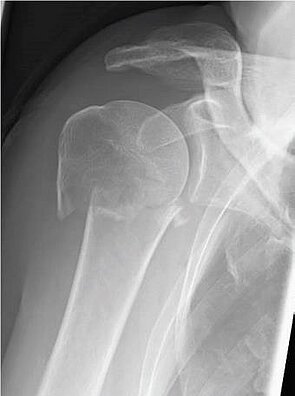

Einen weiteren Schwerpunkt in der Traumabehandlung stellt die Versorgung von Schulterbrüchen dar.

Während bei jüngeren Patienten die Rekonstruktion von Knochen und Gelenken im Vordergrund steht, führt bei älteren Patienten häufig der Gelenkersatz zur schnelleren Wiederherstellung der Beweglichkeit.

Hierfür kann die umfangreiche Erfahrung der orthopädischen Klinik in der Schulterendoprothetik angewandt werden. Dazu werden die Art der Endoprothese und die Einsatzmöglichkeit individuell geplant und umgesetzt.